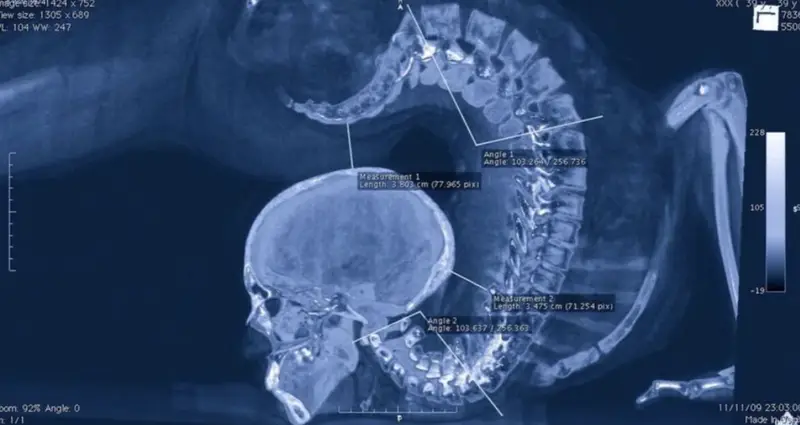

#4 Zlomil si sánku počas jazdy na bicykli